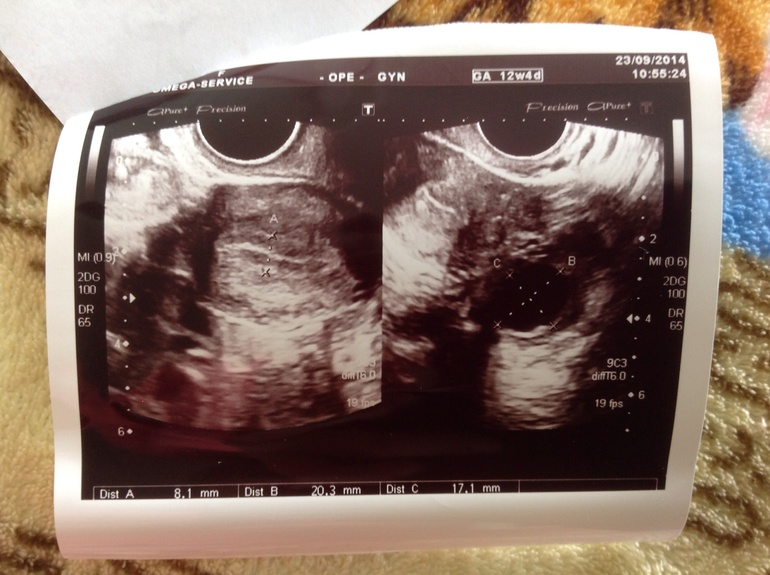

Сходила сегодня на фоликуллометрию,в этот цикл хочу О отследить по узи,мне врач какой то молчаливый попался(((вот теперь гадаю когда мне в след раз идти на узи как считаете?хотим прям в день овуляции попасть

У Вас же уже ЖТ есть,при чём большое.......правда жидкости нет в позадиматочном пространстве.....

Кажется Вам нужно срочно сменить узиста!)))))))Это что-то с чем-то!))))))Обычно если будет овуляция пишут доминантный фолликул,сколько мм он и в каком яичнике и исходя из его размеров,определяют на какой день цикла ещё нужно прийти,чтобы проверить лопнул он или нет! А желтое тело у вас уже есть,если он всё правильно написал.......может он перепутал чего....И учитываю,что у Вас нет жидкости в позадиматочном пространстве, О была 2-3 дня назад!!!Кажется этот узист полный лопух!

эх картинку бы этого тела.. моя Г говрит. что иногда ДФ и ЖТ могут спутать. температуру меряете? если это ДФ, то через 1-2 дня будет О. если это и правда ЖТ, то можно сходить через 4-5 дней посмотреть на его развитие. или сдать прогестерон...

По заключению овуляция у вас уже была , есть ЖТ